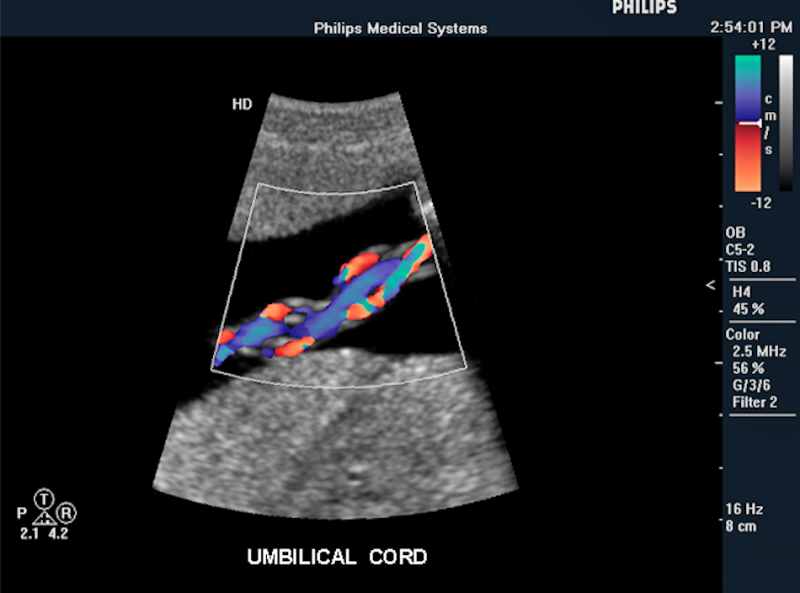

Below is a collection of prenatal ultrasound pictures from the Imaging Technology News (ITN) archive. Use the arrows to click through the image gallery. It includes transvaginal ultrasound images and fetal echocardiogram images. Fetal imaging is referred to by many names, including pregnancy sonograms, pregnancy ultrasound, endovaginal ultrasound, obstetric ultrasound, OB ultrasound, baby ultrasound, prenatal ultrasound. Fetal heart ultrasound is also called baby echo or prenatal echo.